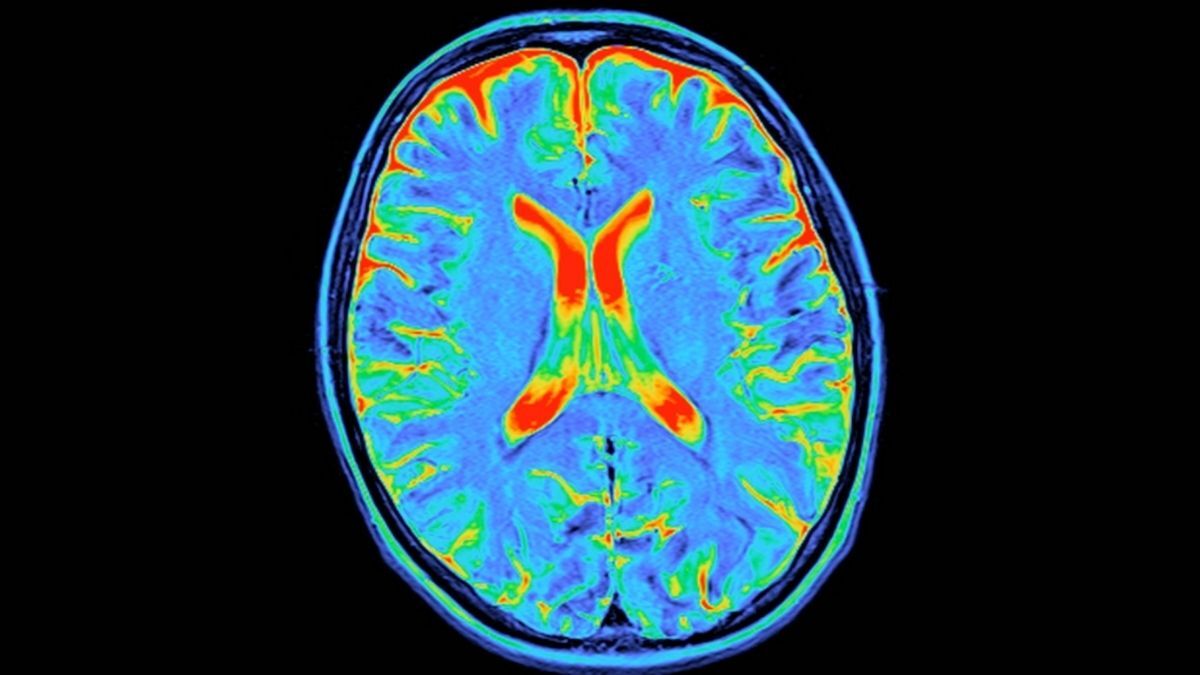

According to the MRI brain scans of 3,802 neurotypical people between infancy and 90 years old, the architecture of the human brain takes a distinct turn at four ages.

These are around 9, 32, 66, and 83 years old, and they mark five epochs: childhood, adolescence, adulthood, early aging, and late aging.